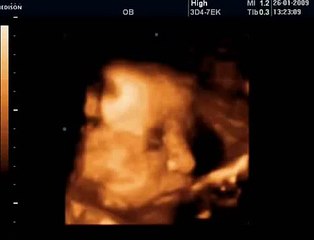

Yeni doğan Suriyeli bebek hava ambulansı ile sevk edildiKARABÜK'te, yemek borusu gelişmemiş şekilde doğan, aynı zamanda yemek borusu ile akciğer arasında delik olan Suriye uyruklu Albatol Al Ghars, solunum sıkıntısı ve yemek borusu tıkanıklığı nedeniyle hava ambulansıyla Ankara'ya sevk edildi. brYeni doğan Suriyeli bebek hava ambulansı ile sevk edildibrbrKARABÜK'te, yemek borusu gelişmemiş şekilde doğan, aynı zamanda yemek borusu ile akciğer arasında delik olan Suriye uyruklu Albatol Al Ghars, solunum sıkıntısı ve yemek borusu tıkanıklığı nedeniyle hava ambulansıyla Ankara'ya sevk edildi.brbrKarabük Eğitim ve Araştırma Hastanesi'nde dün dünyaya gelen Albatol Al Ghars, solunum sıkıntısı nedeniyle tedaviye alındı. Solunum cihazına bağlanan bebek, durumu ağırlaşınca sevk edilmesi kararlaştırıldı. Sağlık Bakanlığı'ndan talep edilen hava ambulansı İl Jandarma Komutanlığı helikopter pistine iniş yaptı.